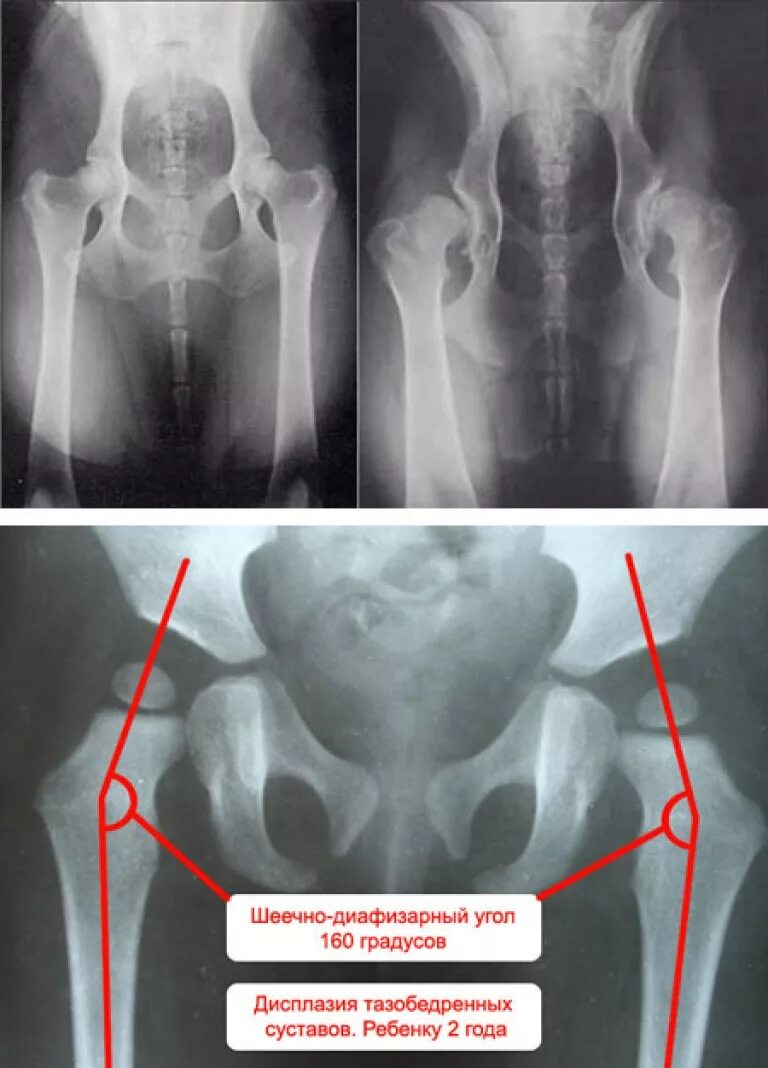

Дисплазия 7 лет